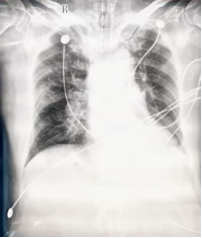

2025/11/23床旁胸片

2025/11/23床旁胸片:1.肺水肿可能,较2025-11-20DR改善,请结合临床及实验室检查2.左侧胸腔积液3.双侧多发肋骨走行欠规整,结合病史